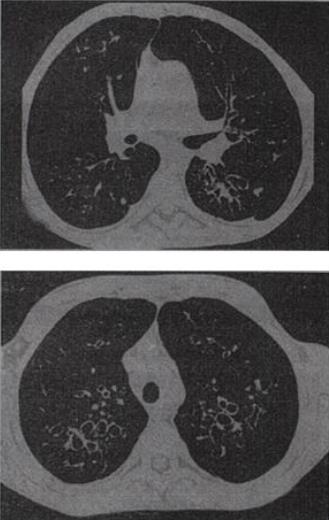

患者,男,38岁,咳嗽、咳痰、咯血,结核菌素实验(-),结合CT图像,最可能的诊断是()。

A、支气管扩张

B、肺囊虫病

C、肺囊肿

D、间质性肺炎

E、特发性肺间质纤维化

A